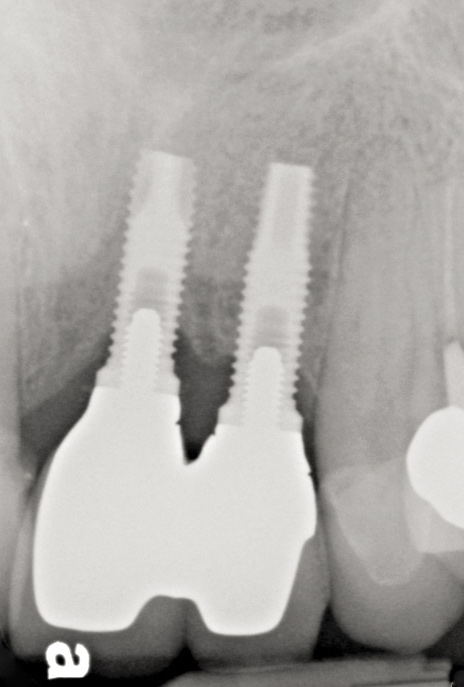

Fig 49. Clinical presentation of implants that were placed with insufficient inter-implant distance. Forced eruption would not have been appropriate in this situation because the interproximal biologic width was violated.

Figure 49

Fig 50. Note the lack of interproximal papilla height between implants Nos. 9 and 10.

Figure 50

Fig 51. Radiograph of implants placed with insufficient inter-implant distance in Figure 49 and Figure 50 with attachment loss.

Figure 51